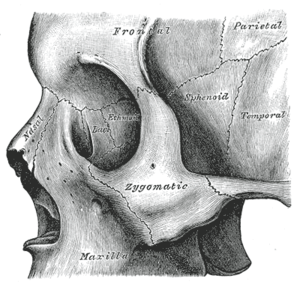

The nasal articulates with four bones: two of the cranium, the frontal and ethmoid, and two of the face, the opposite nasal and the maxilla.

Right nasal bone. Inner surface. Close up of side view of the skull.

Close up of side view of the skull. Side view of the skull.